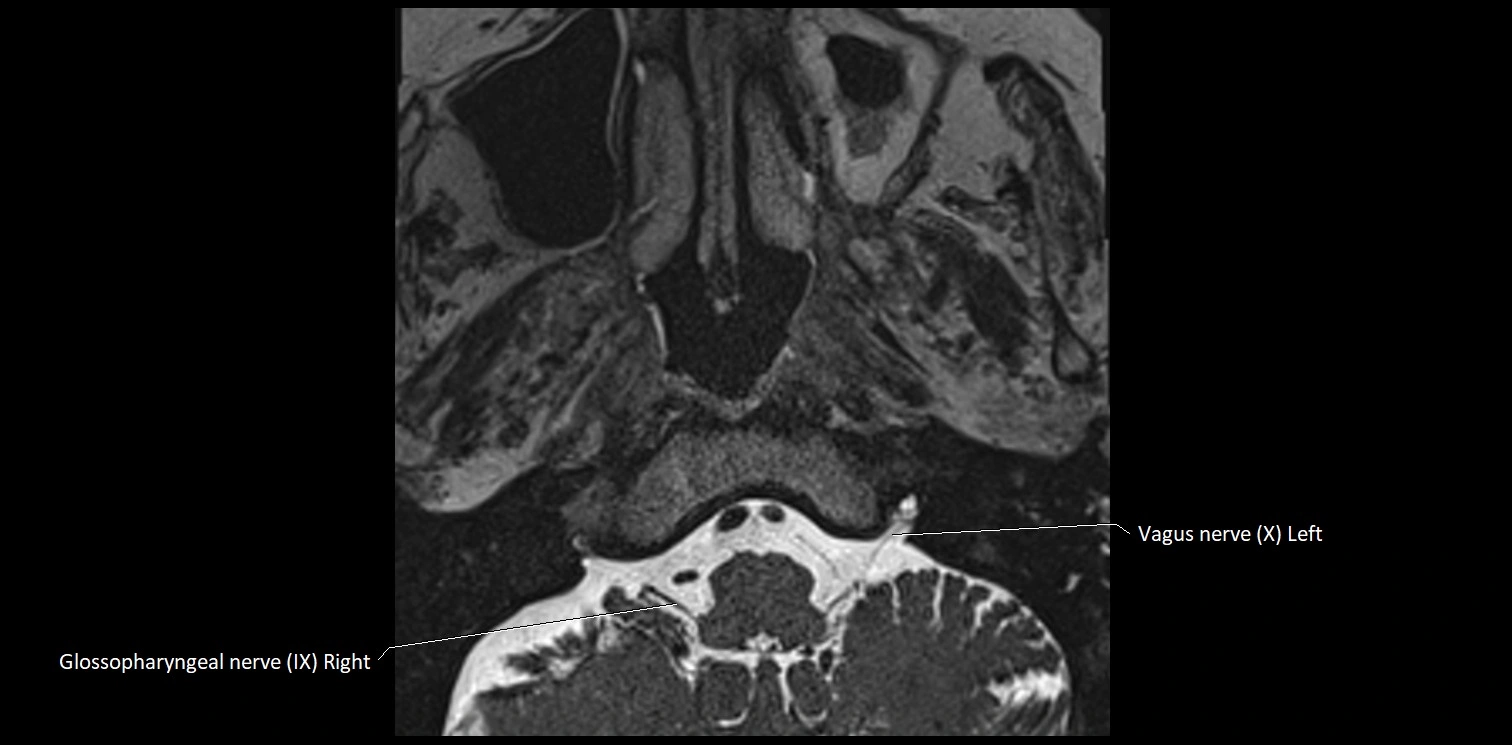

MRI Appearance

• The abducens nerve is a small, thin, linear structure

• Best visualized on high-resolution T2-weighted 3D MRI sequences (e.g., FIESTA or CISS)

• Seen as a hypointense (dark) line running from the brainstem at the pontomedullary junction, traversing the prepontine cistern, and entering Dorello’s canal under the petrosphenoidal ligament, then into the cavernous sinus, and finally the orbit

• May be challenging to visualize in standard MRI due to its small size

• Pathology may be inferred by absence, displacement, or enhancement of the nerve

MRI images

image